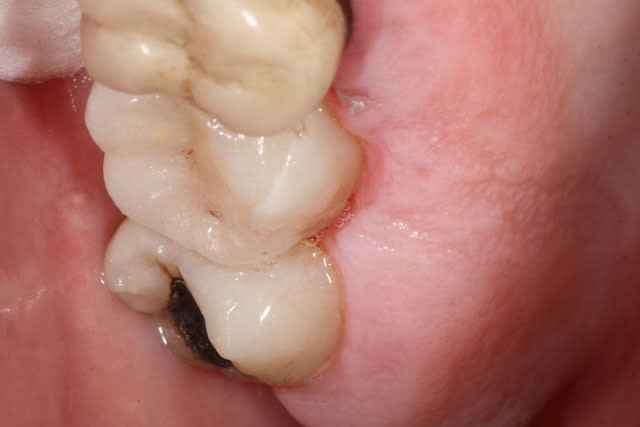

Dent vitale. Il y avait un compo OD et le pan V a lâcher. Limite supra-gingivale.

Ci joint une autre vue.

Petite question, par curiosité: la cavité a l'air profonde sous la gencive, non?

La cavité d'accès pour une dévit est insuffisante , la dent est vivante . La limite de la cavité est sus gingivale .